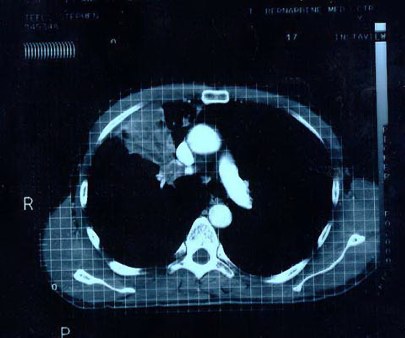

Scan 15th March 1999 No4